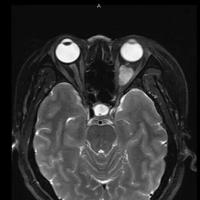

女,54岁,头痛头晕月余,无眼部症状及视力异常。 影像表现:右侧眼球后方占位病变,考虑海绵状血管瘤可能性大,鉴别:视神经鞘瘤、脑膜瘤及炎性假瘤。 病例点评:眼眶内血管瘤是较常见的良性肿瘤,其中以海绵状血管瘤最常见。可发生于任何年龄,主要表现为眼球突出及偏位,在低头或哭泣时可有突眼加重。可经眶缘触及具有压缩性的肿块。视力损害多较缓慢。肿块大多位于肌锥内,其次为肌锥外,平扫呈边界清楚的圆形、卵圆形或分叶状肿块,增强扫描呈缓慢进行性显著强化为其特征性表现。